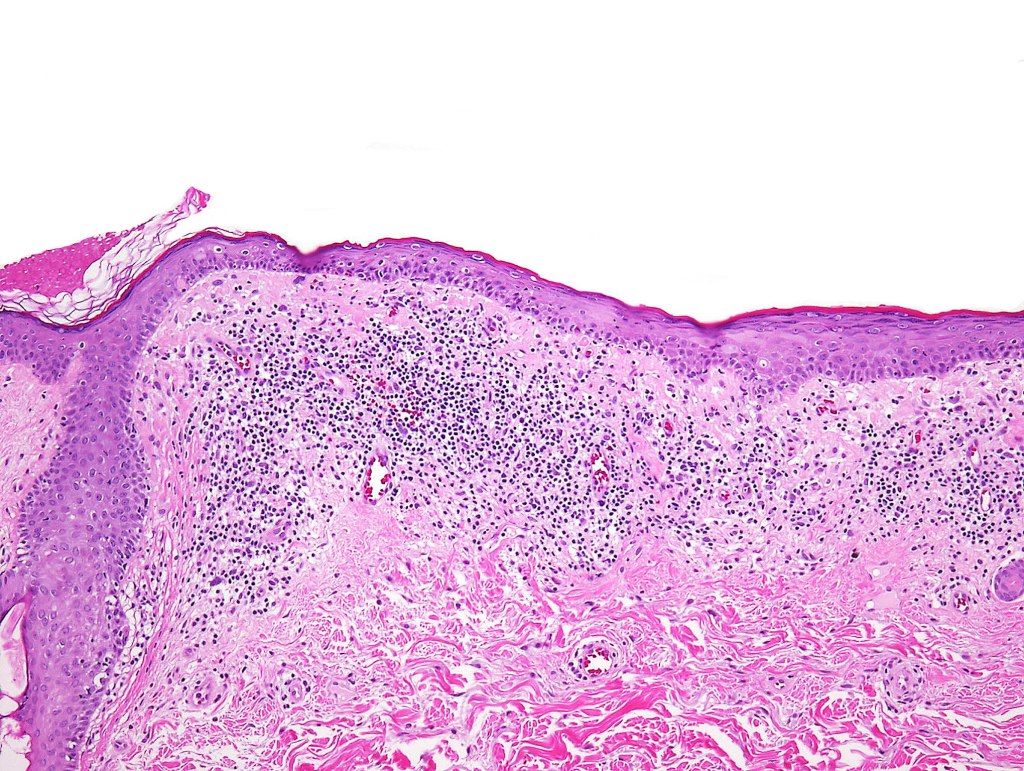

•Hyperkeratosis +/- parakeratosis

•Wedge-shaped hypergranulosis

•Generally irregular (sometimes saw-tooth) acanthosis but may show broad acanthosis

•Interface change

•Conspicuous cytoid bodies

•Pigment incontinence

•Band-like or perivascular infiltrate of lymphocytes, histiocytes with occasional eosinophils & plasma cells